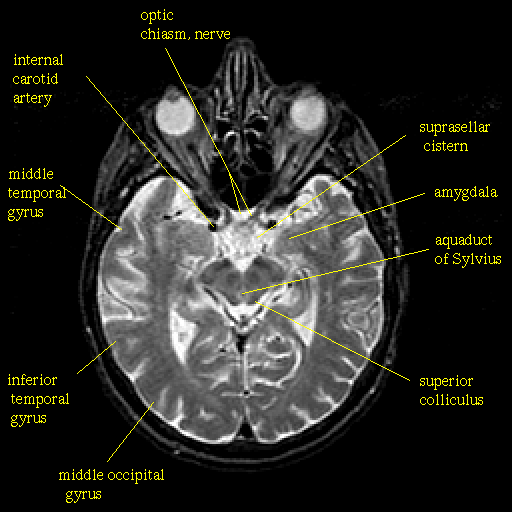

The image below shows a frontal section, that is down on the brain from above, at the level indicate by the small figure to the left of (or if your resoution is low it might show up above) the main image. Clicking on the terms will send you to a definition of the term as it is found in a larger list of Neuropsychological terms.

Images are from the The Whole Brain Atlas.